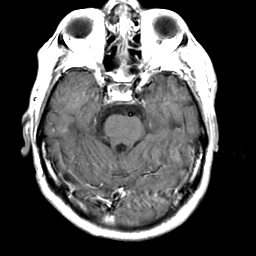

Meningioma, MR Study #2 -- Slice #6

[Home][Help][Clinical] Slice 6